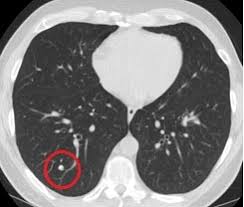

Can You Detect Lung Cancer With Ct Scan - Detection Of Early Stages Of Lung Cancer Based On Imaging A Download Scientific Diagram - Your doctor might use imaging tests to look for unusual growths inside your body that might be cancer.. It can also show whether the cancer has spread outside the lung. It gives detailed information about your cancer. Ct scans of the chest are used to find lung nodules or other chest pathology. Therefore, ct scans can lead to a false negative this can negatively impact your ability to get any treatment at all If cancer is diagnosed, other tests will be performed to stage and grade the tumor so that the appropriate treatment can be delivered.

Once a nodule is found, a workup is done to see if it is cancer. This can include a chest computed tomography (ct) scan and, if a nodule or mass is found, a biopsy. A ct scan is one of several diagnostic tests that physicians order when they suspect lung cancer. The amount of radiation you're exposed to during an ldct is much less than that of a standard ct scan. If the test finds cancer, treatment can start early.

A ct scan test can also be used to look for the spread of lung cancer in the adrenal. Once a nodule is found, a workup is done to see if it is cancer. It is used to look for early signs of lung cancer. Ct scans of the chest are used to find lung nodules or other chest pathology. Awareness of the possible causes of overlooking a pulmonary lesion can give radiologists a chance to reduce the occurrence of this eventuality. This can provide definitive evidence of the disease. If you are a smoker, it is highly recommended to have a ct scan every 3 months. It gives detailed information about your cancer. It's equal to about half the radiation you're exposed to naturally from the environment in a year. Another doctor might be able to recommend other testing options. Your doctor might use imaging tests to look for unusual growths inside your body that might be cancer. Computed tomography (ct) scans detect tumors, but do not determine whether they are malignant or not. The doctor will then order additional testing to rule out or confirm a cancer diagnosis.

But the test is not helpful for light smokers or people who quit smoking more than 15 years ago. Early detection of lung cancer means more treatment options an excellent tool for people at high risk for lung cancer the scan is quick, painless and noninvasive ct imaging is detailed and accurate and can reveal the smallest of abnormalities The scan looks at your lungs and other parts of your chest. Ct is highly accurate for lung cancer detection. Nevertheless, lung cancer can also be overlooked on computed tomography (ct) scans, regardless of the context, either if a clinical or radiologic suspect exists or for other reasons. A ct scan test can also be used to look for the spread of lung cancer in the adrenal. If you are at higher risk, talk to your doctor about getting screened. The smallest recesses of the chest can be clearly seen. It can also show the size, shape, and position of any lung tumors and can help find enlarged lymph nodes that might contain cancer that has spread. Therefore, ct scans can lead to a false negative this can negatively impact your ability to get any treatment at all Ct scans of the chest are used to find lung nodules or other chest pathology. Alternatively, you should take lung ct scans if you are concerned or if you show any symptoms. It can also look at your liver and adrenal glands.

Ldct scans can help find abnormal areas in the lungs that may be cancer. It can also look at your liver and adrenal glands. It can show the size, shape, position, and depth of any lung tumor. Nevertheless, lung cancer can also be overlooked on computed tomography (ct) scans, regardless of the context, either if a clinical or radiologic suspect exists or for other reasons. Ct is highly accurate for lung cancer detection.